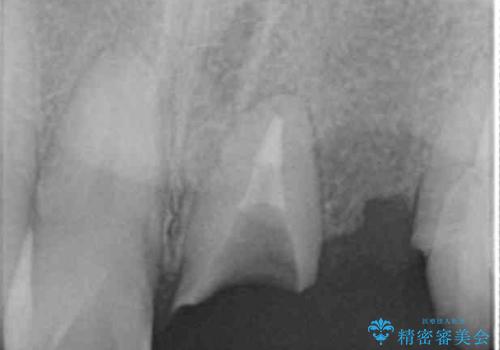

犬歯は歯ぐきの奥深くまで割れており保存不可能な状態でしたが、どうしても抜きたくないとのことでした。

歯を牽引し健全歯質を歯肉縁上まで引き上げ、歯の保存を試みることにしました。

根の長さが短くなるためブリッジの支台歯としては弱いこと、長期的予後は不明なことをご理解頂いた上で治療を行いました。

健全歯質を歯肉縁上に出すためにしっかり挺出させたことで歯根長が短くなりましたが、仮歯で十分に保定した結果動揺度Ⅰ程度となり、ブリッジの支台歯にすることが可能と判断しました。